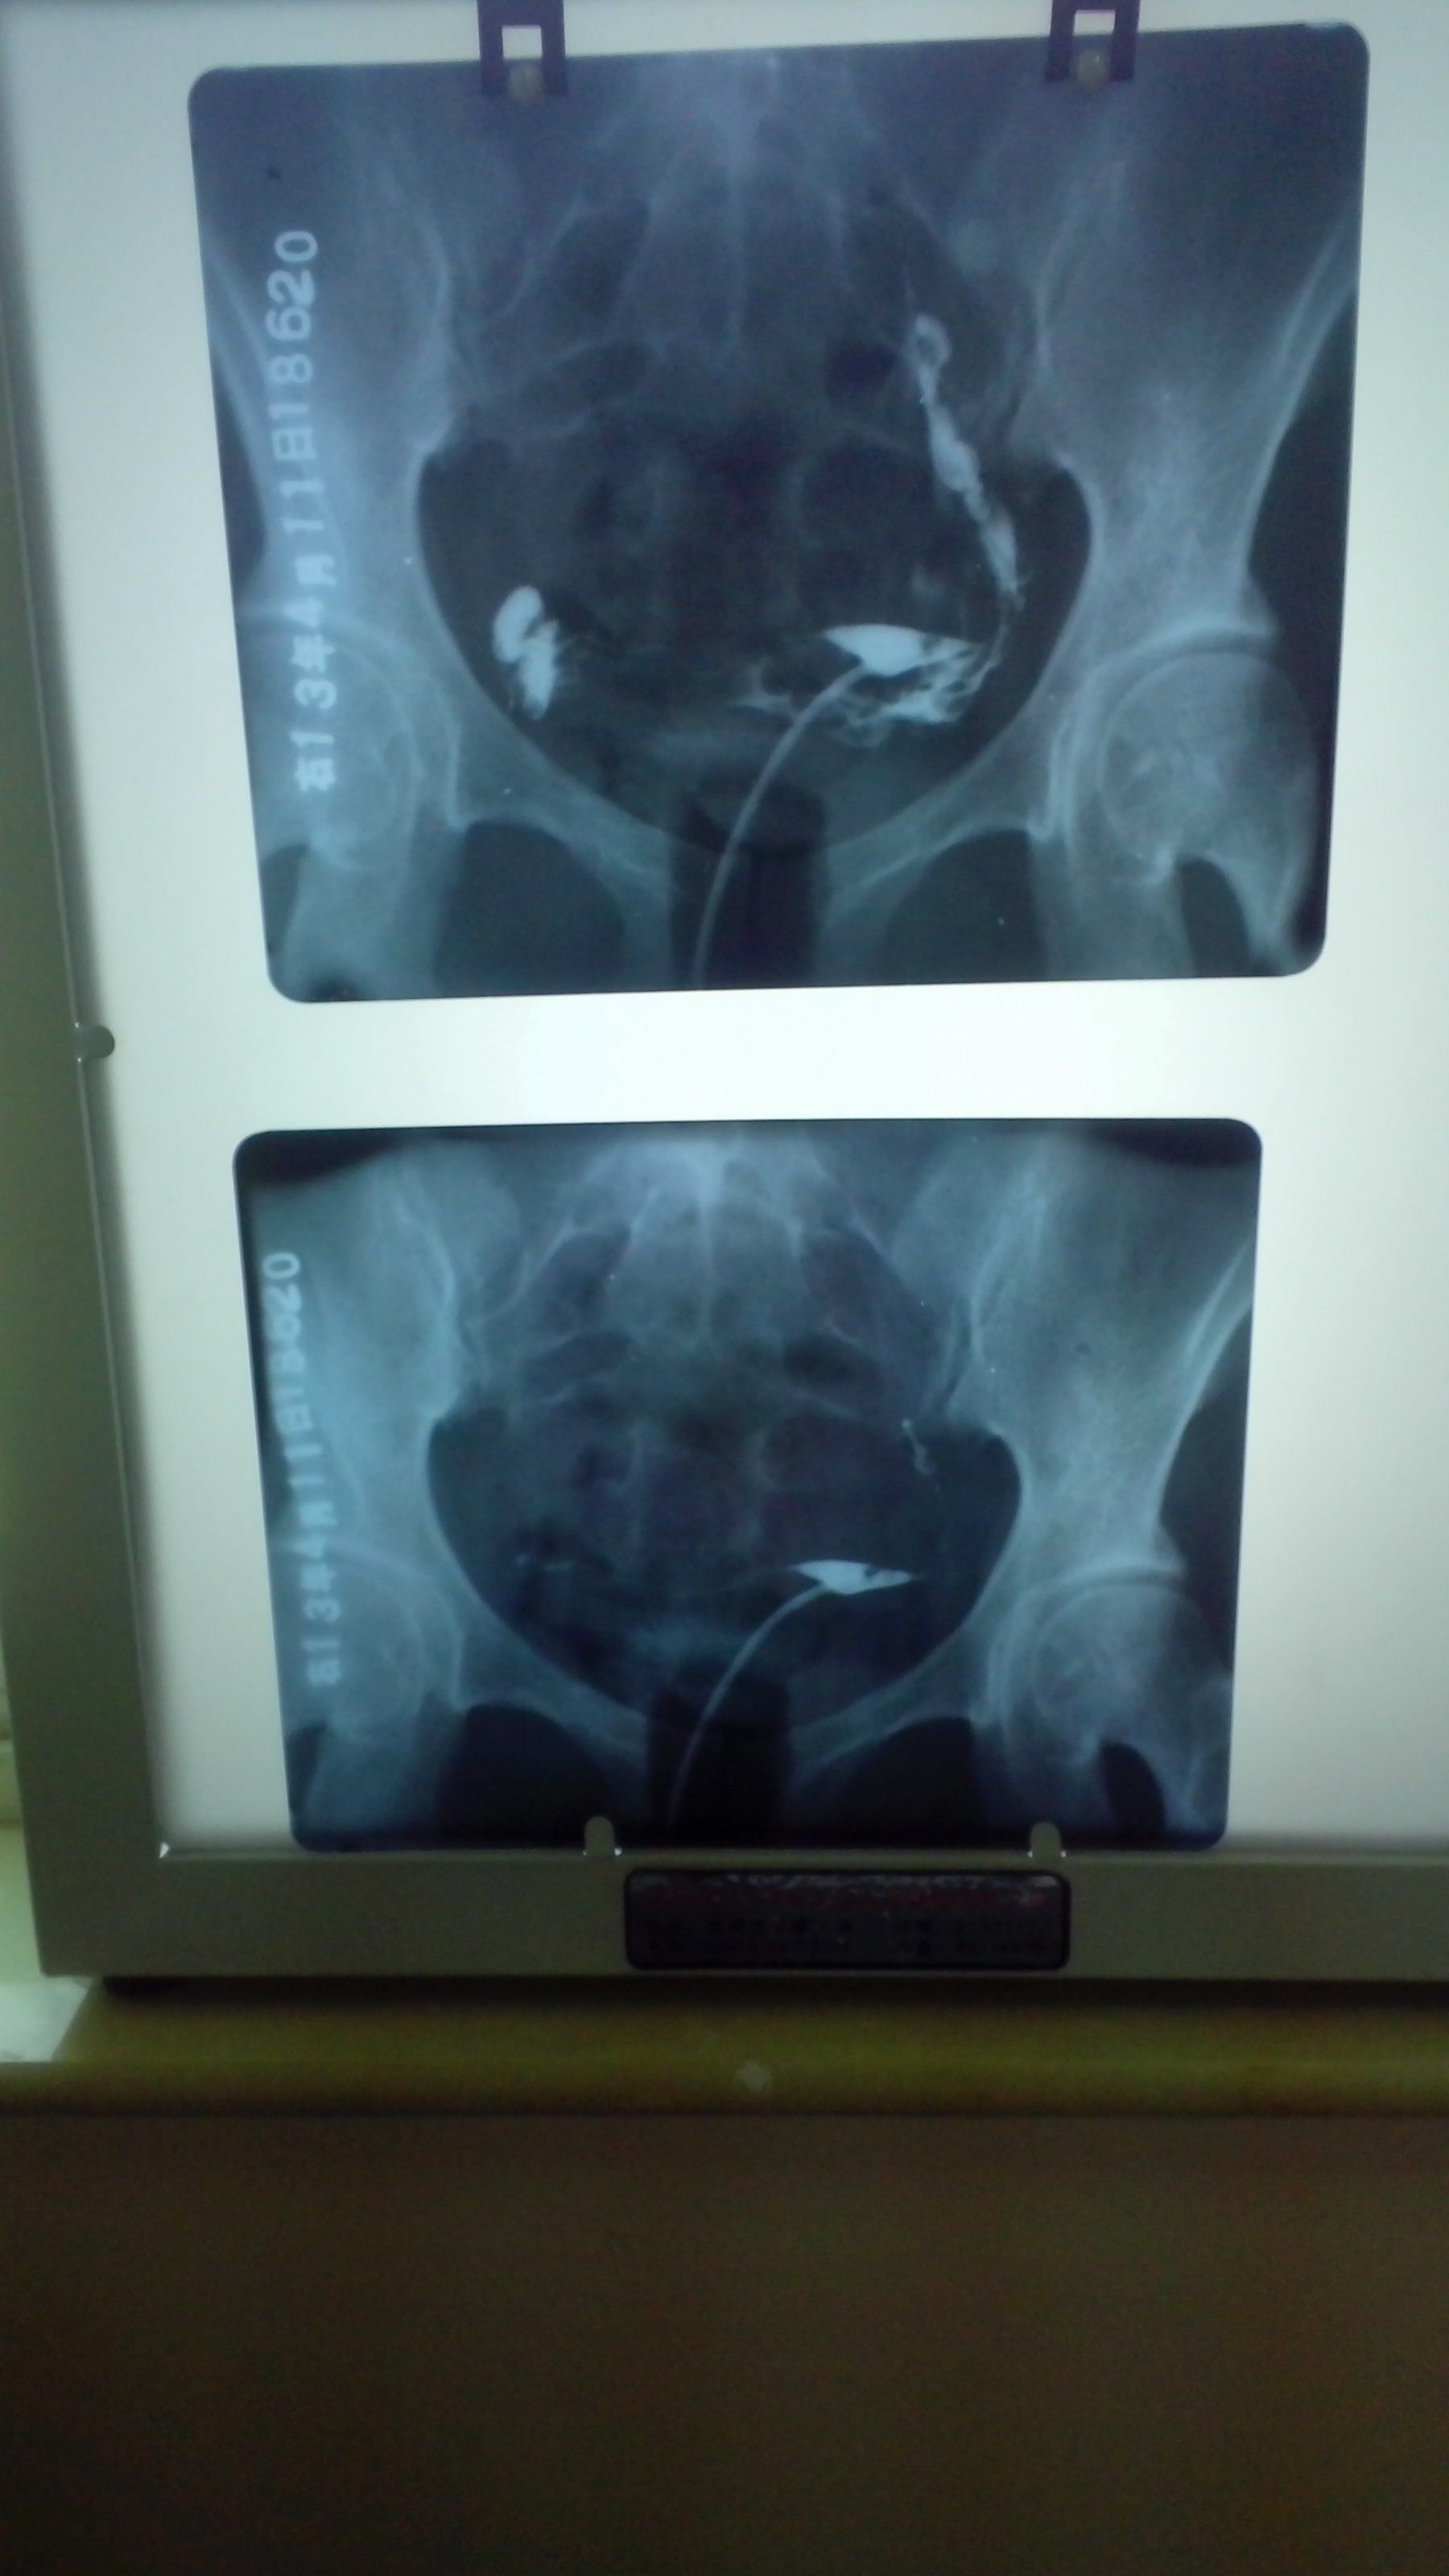

9年前宫外孕做了保留输卵管手术,今年检查,医生说右侧输卵管伞端积水,左则输卵管上举,不想手术怎么办 这是造影报告,能否用自身调理恢复,不想手术 点击展开 匿名用户 2013-05-15 22:34 满意回答 左侧是可以不手术的,但是右侧最好手安缘术治疗,如果没有生育要评葛求,也无明显不适症状的话,可以继续观了筛贸察。 匿名用户 2013-05-15 23:22 宝宝知道提示您:回答为网友贡献,仅供参考。 相关问题 宫外孕开刀手术保留输卵管,发现右侧输卵管右积水,已处理我怀孕机率有多大? 有没有宝妈和我一样五周去做B超,显示宫内没胎儿,而输卵管间歇处长了个不知是什么,医生也不确定宫外孕 怀孕初期,喝鲫鱼汤能治输卵管积水吗?防止宫外孕吗?